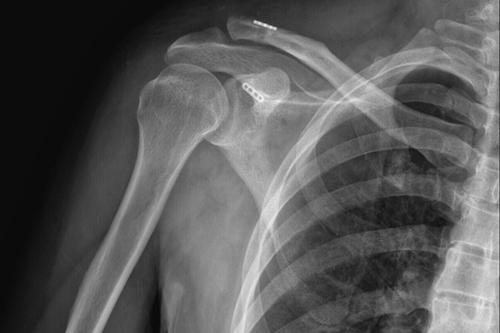

术后DR

一名50岁的男性患者,因不慎摔伤致右肩关节肿痛,并伴活动受限4天后来附院求治。入院查体发现患者右肩部肿胀明显,右锁骨远端隆起畸形,局部明显按压出现疼痛,肩部外展活动受限,进行X线检查显示“右肩锁关节脱位”。骨三科医师团队根据患者病情,进行充分商讨,确定了手术治疗方案,决定为患者实施“右肩锁关脱位复位带袢钢板内固定术”。由副主任医师蒋宇平主刀,骨三科手术团队在患者锁骨上方及喙突处各取2cm手术切口,将肩锁关节复位后,使用瞄准器由喙突基底部向锁骨远端建立骨性隧道,最后将带袢钢板由骨道穿出后固定,术中出血仅10ml左右。